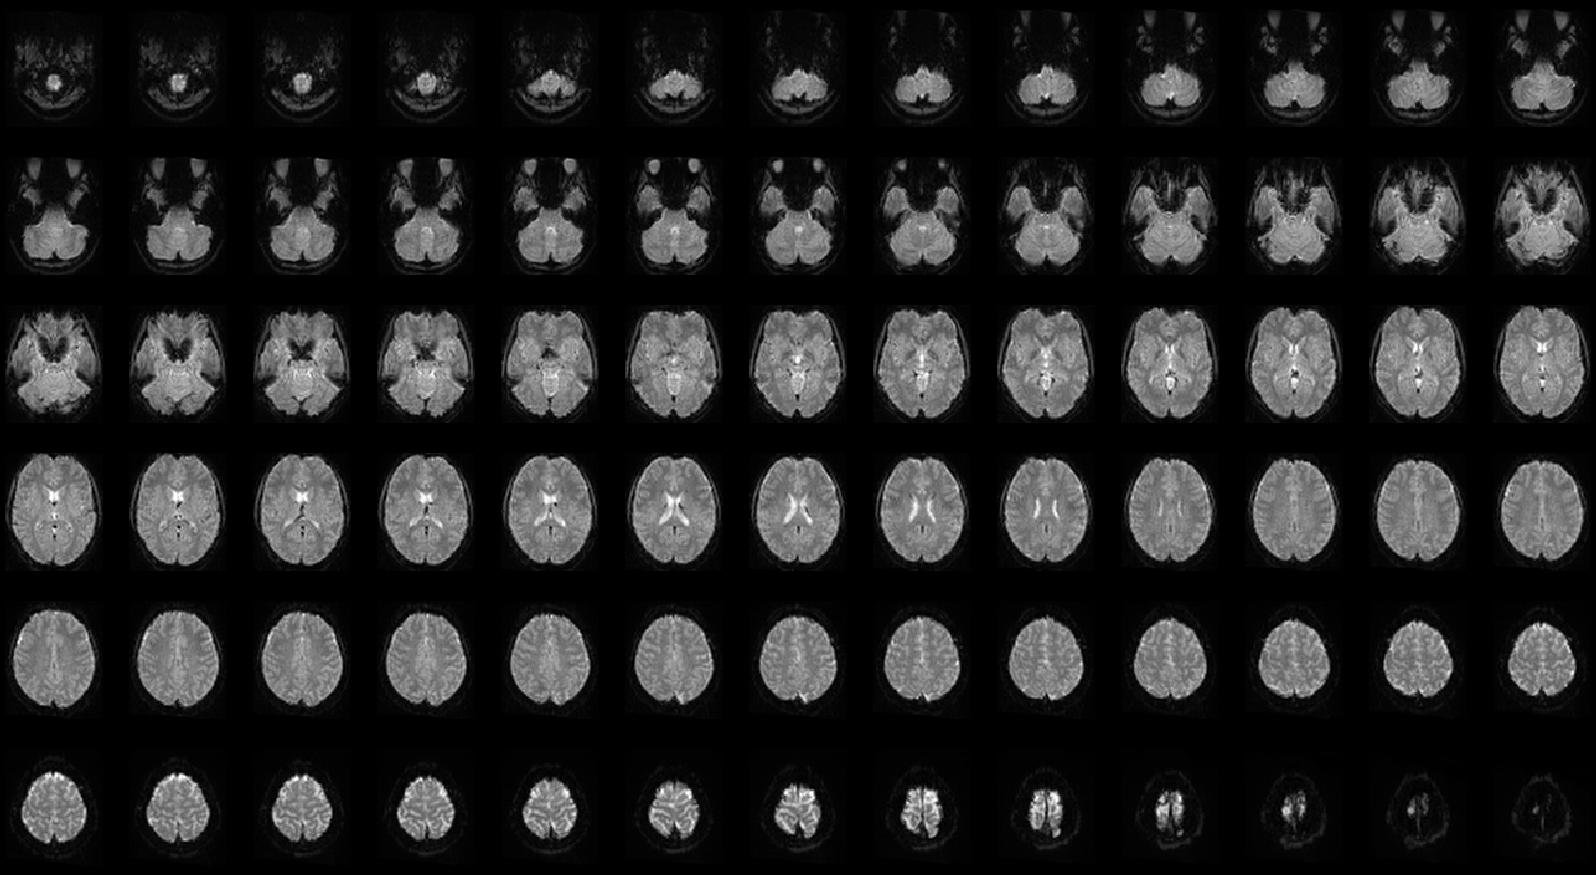

I believe that cognitive neuroscience, the field I am currently engaged in, provides a framework for scientifically answering the question "Who am I?". In our laboratory, a typical method involves measuring human behavior and brain activity and examining the relationship between them. In particular, we measure the brain activity of humans performing psychological tasks using functional magnetic resonance imaging (fMRI; Figure 1).

Functional MRI allows us to measure activity across all regions of the brain, one of the largest organs in the human body, without causing any damage (Figure 2). Using this method, we can investigate which areas of the brain are active, under what conditions, and in what way (Figure 3). This offers the potential to understand the workings of the mind as information processing in the brain. Importantly, this scientific framework solves the problems faced by the pioneers mentioned above by enabling an empirical understanding of the mind.